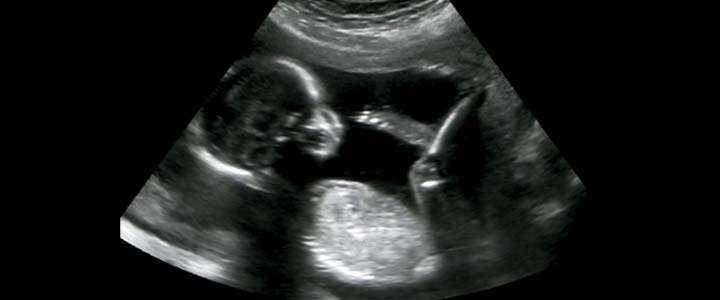

De nekplooimeting is een onderdeel van de combinatietest. Iedere foetus tussen de 11e en 14e weken oud heeft een dun vochtblaasje onder de huid in de nek, dit noemen we de nekplooi. De dikte van de nekplooi varieert met de zwangerschapsduur en is slechts tijdelijk. Deze verdwijnt later in de zwangerschap. Door onderzoek zijn de normale waarden bekend geworden. De nekplooi behoort maximaal 3 mm dik te zijn.

De nekplooimeting gebeurd door een echoscopist die veel ervaring heeft en is bijgeschoold in de specifieke meting. Het gaat bij de meting om millimeters en een kleinste mismeting kan al veel onrust veroorzaken bij de ouders en ook tot onnodig onderzoek leiden. De meting zelf heeft geen enkele (lichamelijke) bijwerking.